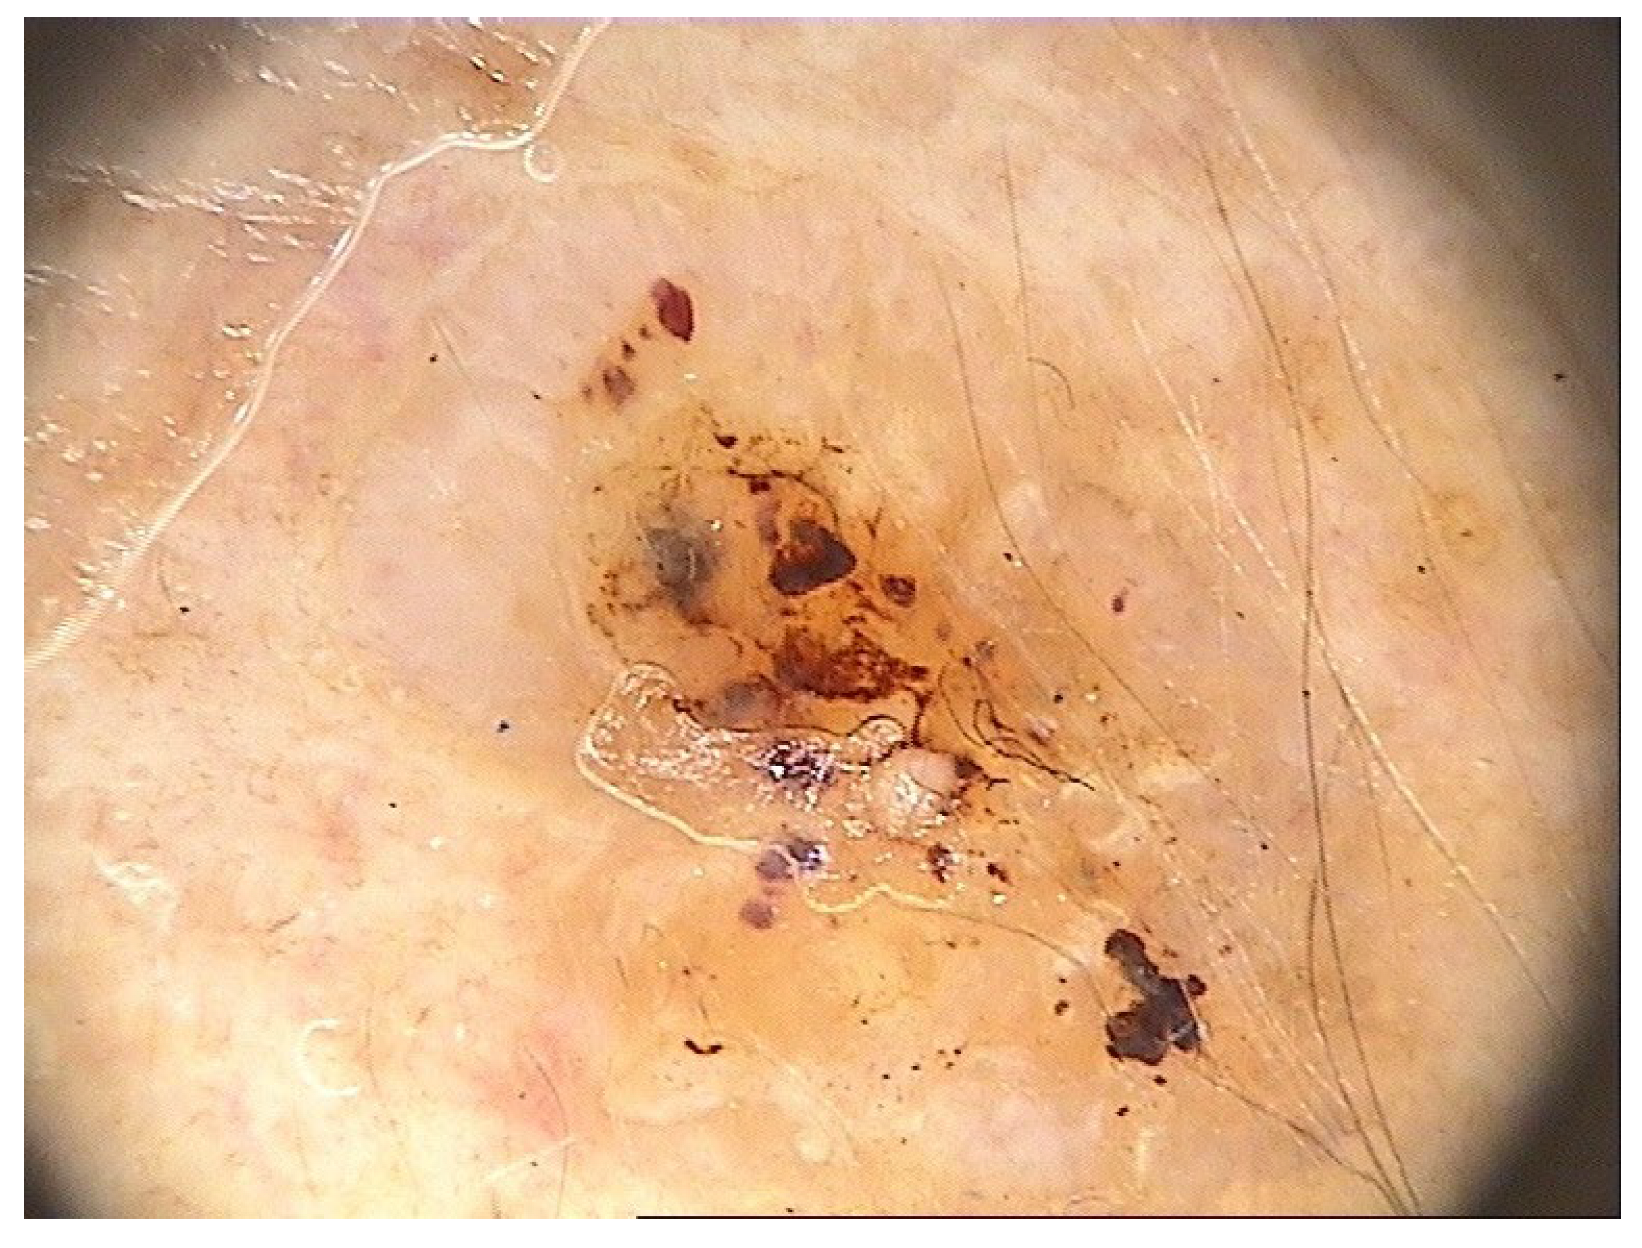

| Cutaneous malignancies | 9 (1.1) |